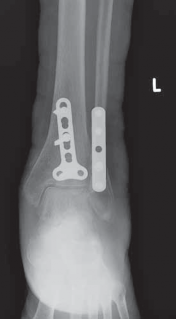

--- TECH FIG 6 • Postoperative AP and lateral radiographs demonstrating posterior plating of the tibia to buttress the posterior malleolar fracture fragment. ### TECHNIQUES